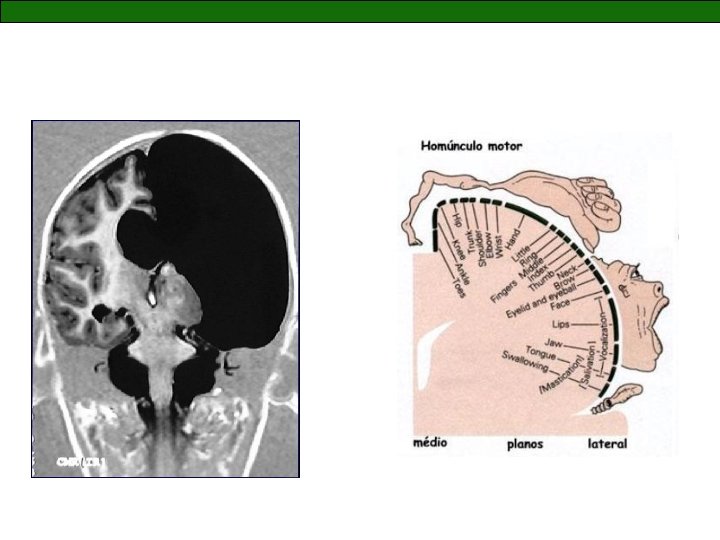

Epilepsias focais sintomáticas

Adolescente com 15 anos de idade • Início de crises epilépticas: 6 anos • Inicialmente, versão cefálica para a esquerda com generalização secundária - duas a três vezes ao dia • Mudança nos padrões semiológicos: crise parcial simples (aura cefálica) e parcial complexa - duas vezes por semana

Criança com 3 anos e 9 meses de idade • Início de crises epilépticas há 2 anos • Crises diárias, predomínio noturno • Desenvolvimento normal

LMVP, 9 anos • desenvolvimento normal • início epilepsia: 3 anos • crises hemigeneralizadas à direita - clonias/ hipertonia em hemicorpo direito • aura indefinida a partir de 5 anos • Uso prévio: PB, CBZ, VPA • Uso atual: TPM (4, 5), OCBZ (36) – crises diárias Exame neurológico/ neuropsicológico - hemiparesia à direita (grau 4) - mão funcionante, anda sem limitações - QIG 74/ QIV 73/ QIE 81